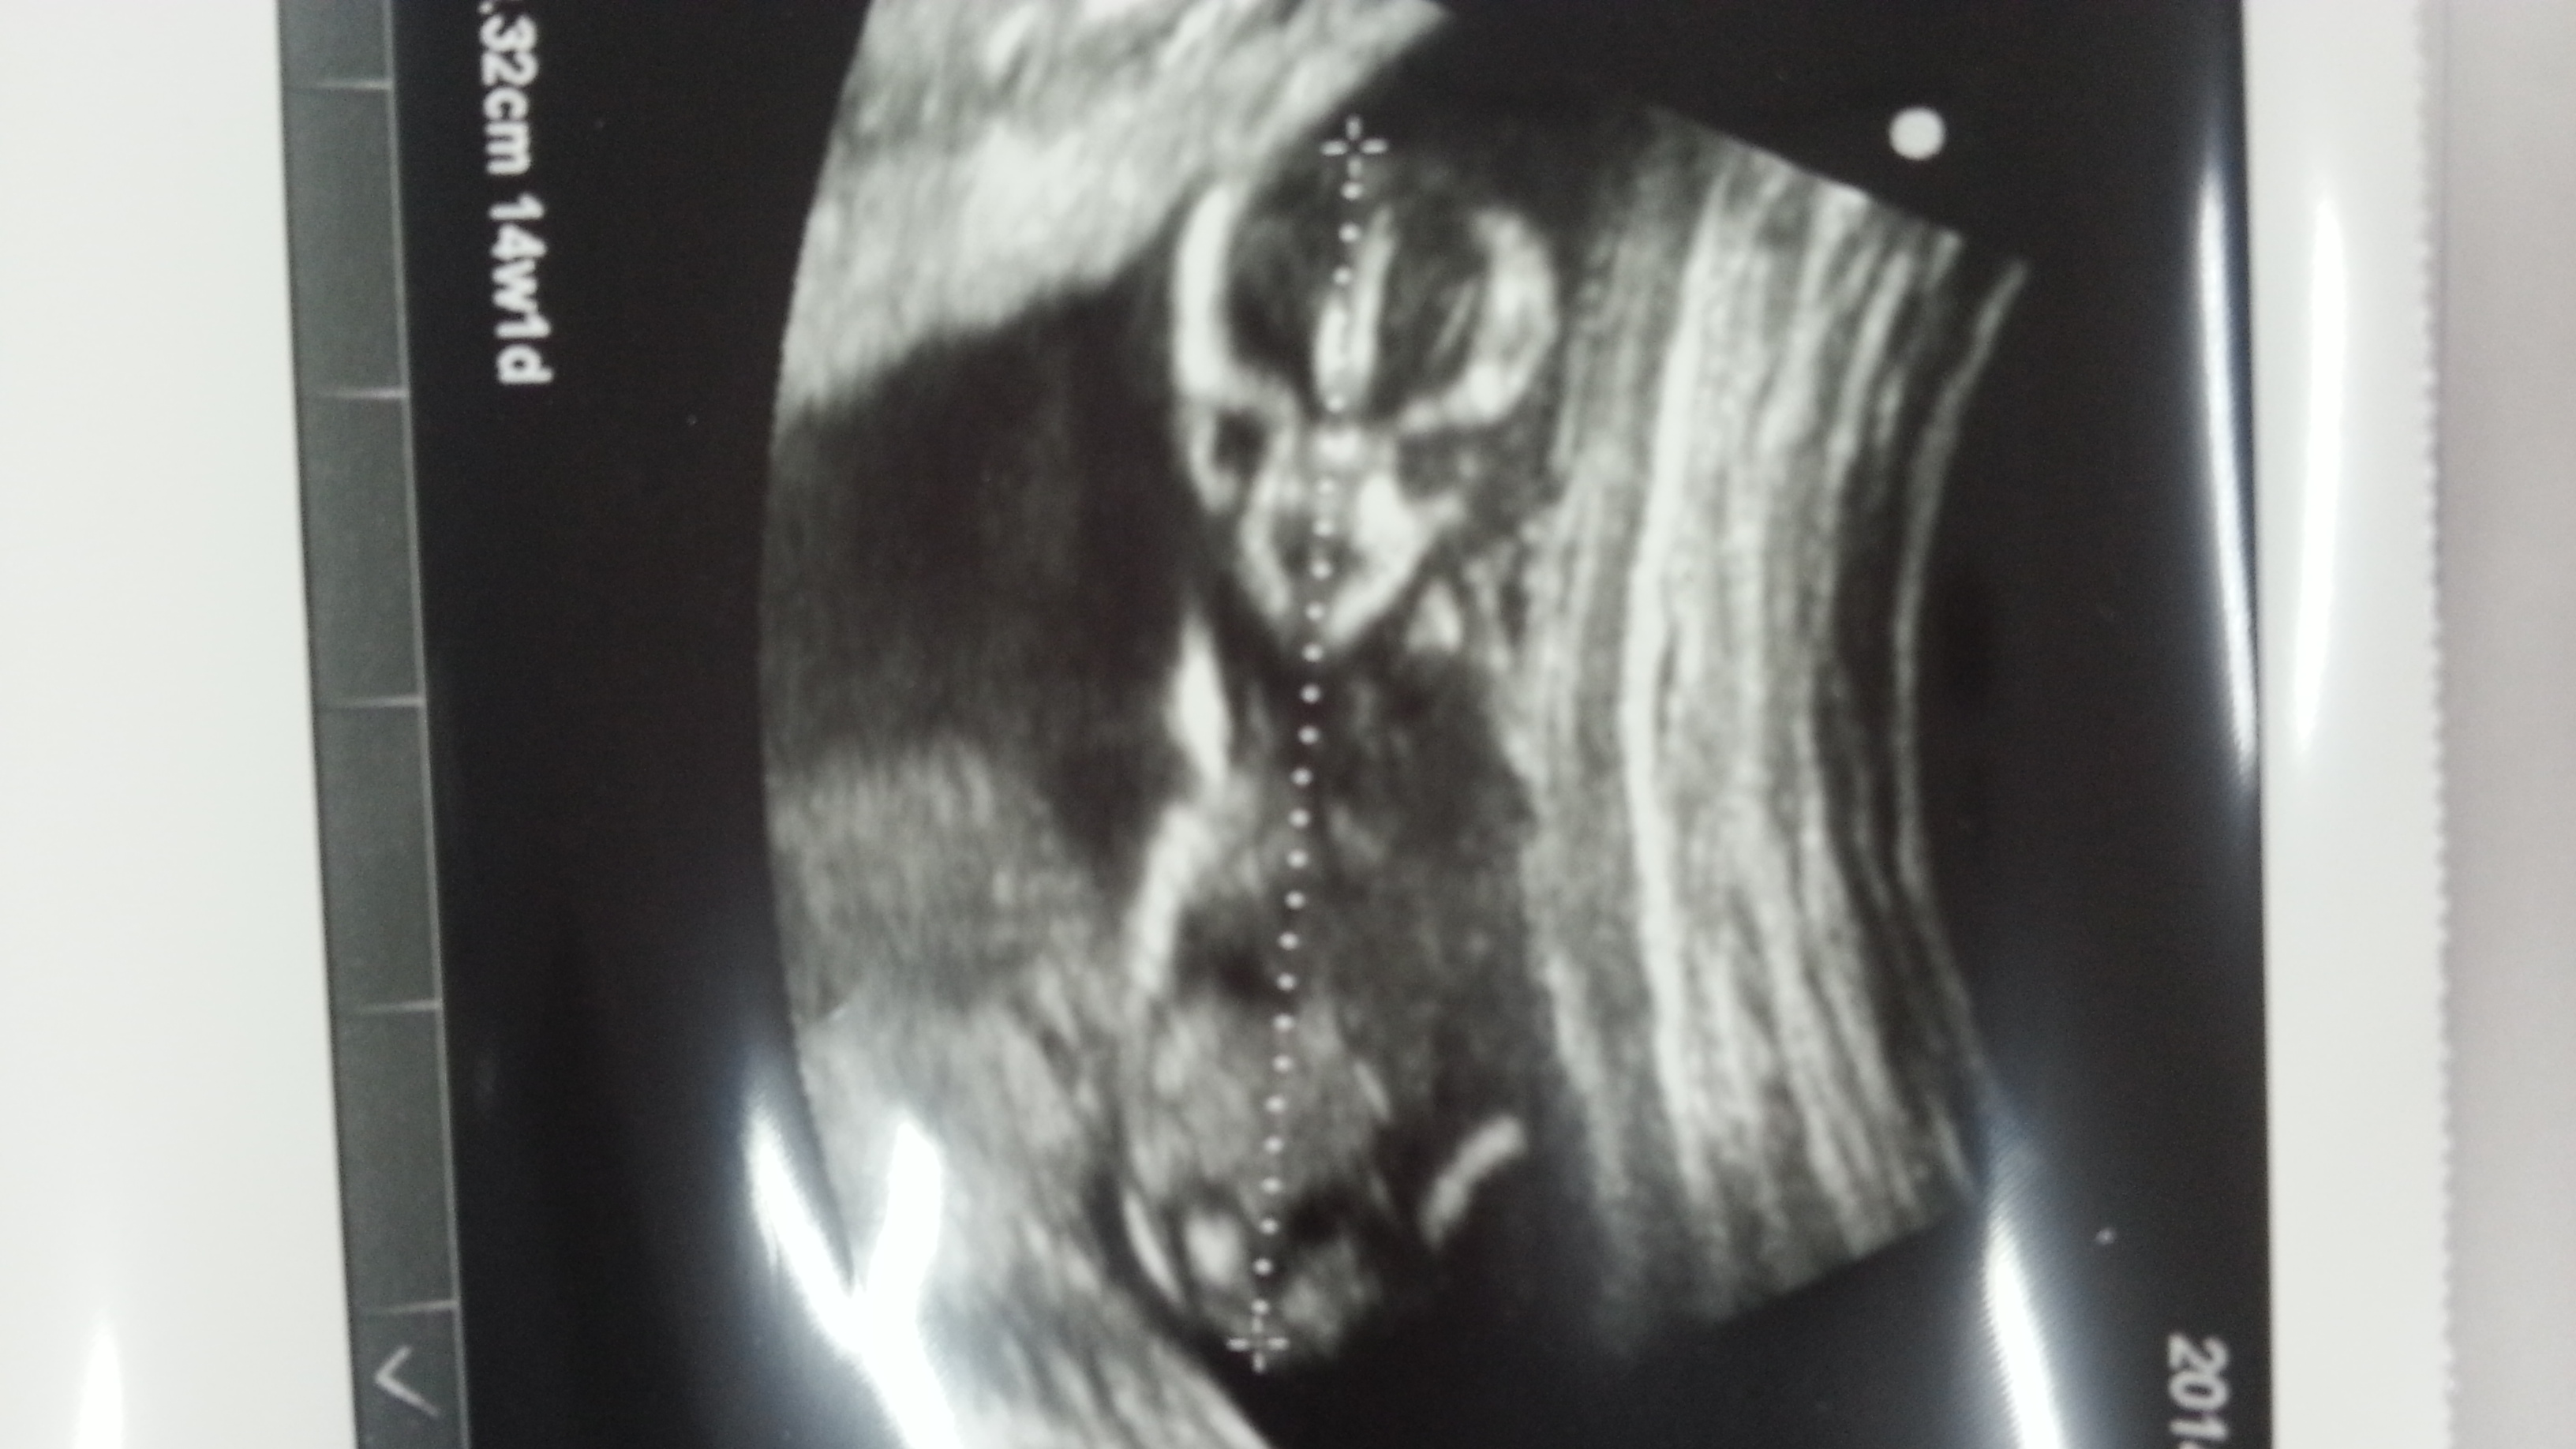

i found some 2D ones, does it help? :)

here it is again:)

Attachment 22047

Maybe maybe girl :)

Thats the view we need to see! Any more like this one?? THe nub isn't really showing but I would guess girl off of the fact that at 12w 6d a boy nub might be more obvious, but it is really a guess 55/45 maybe :)

I think that's a girl x